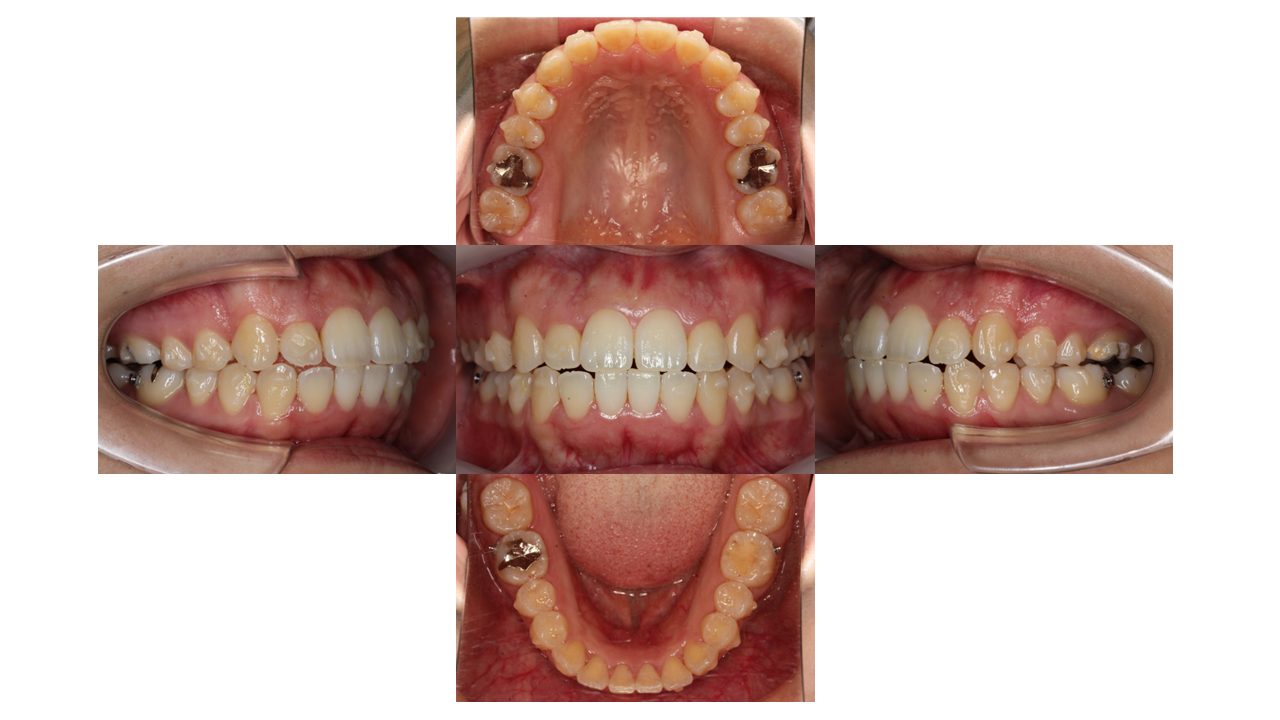

1年1か月経過の口腔内の状態です。

前歯の凸凹が、全て改善しました。

噛み合わせなど、細かい部分の調整をしていきます。